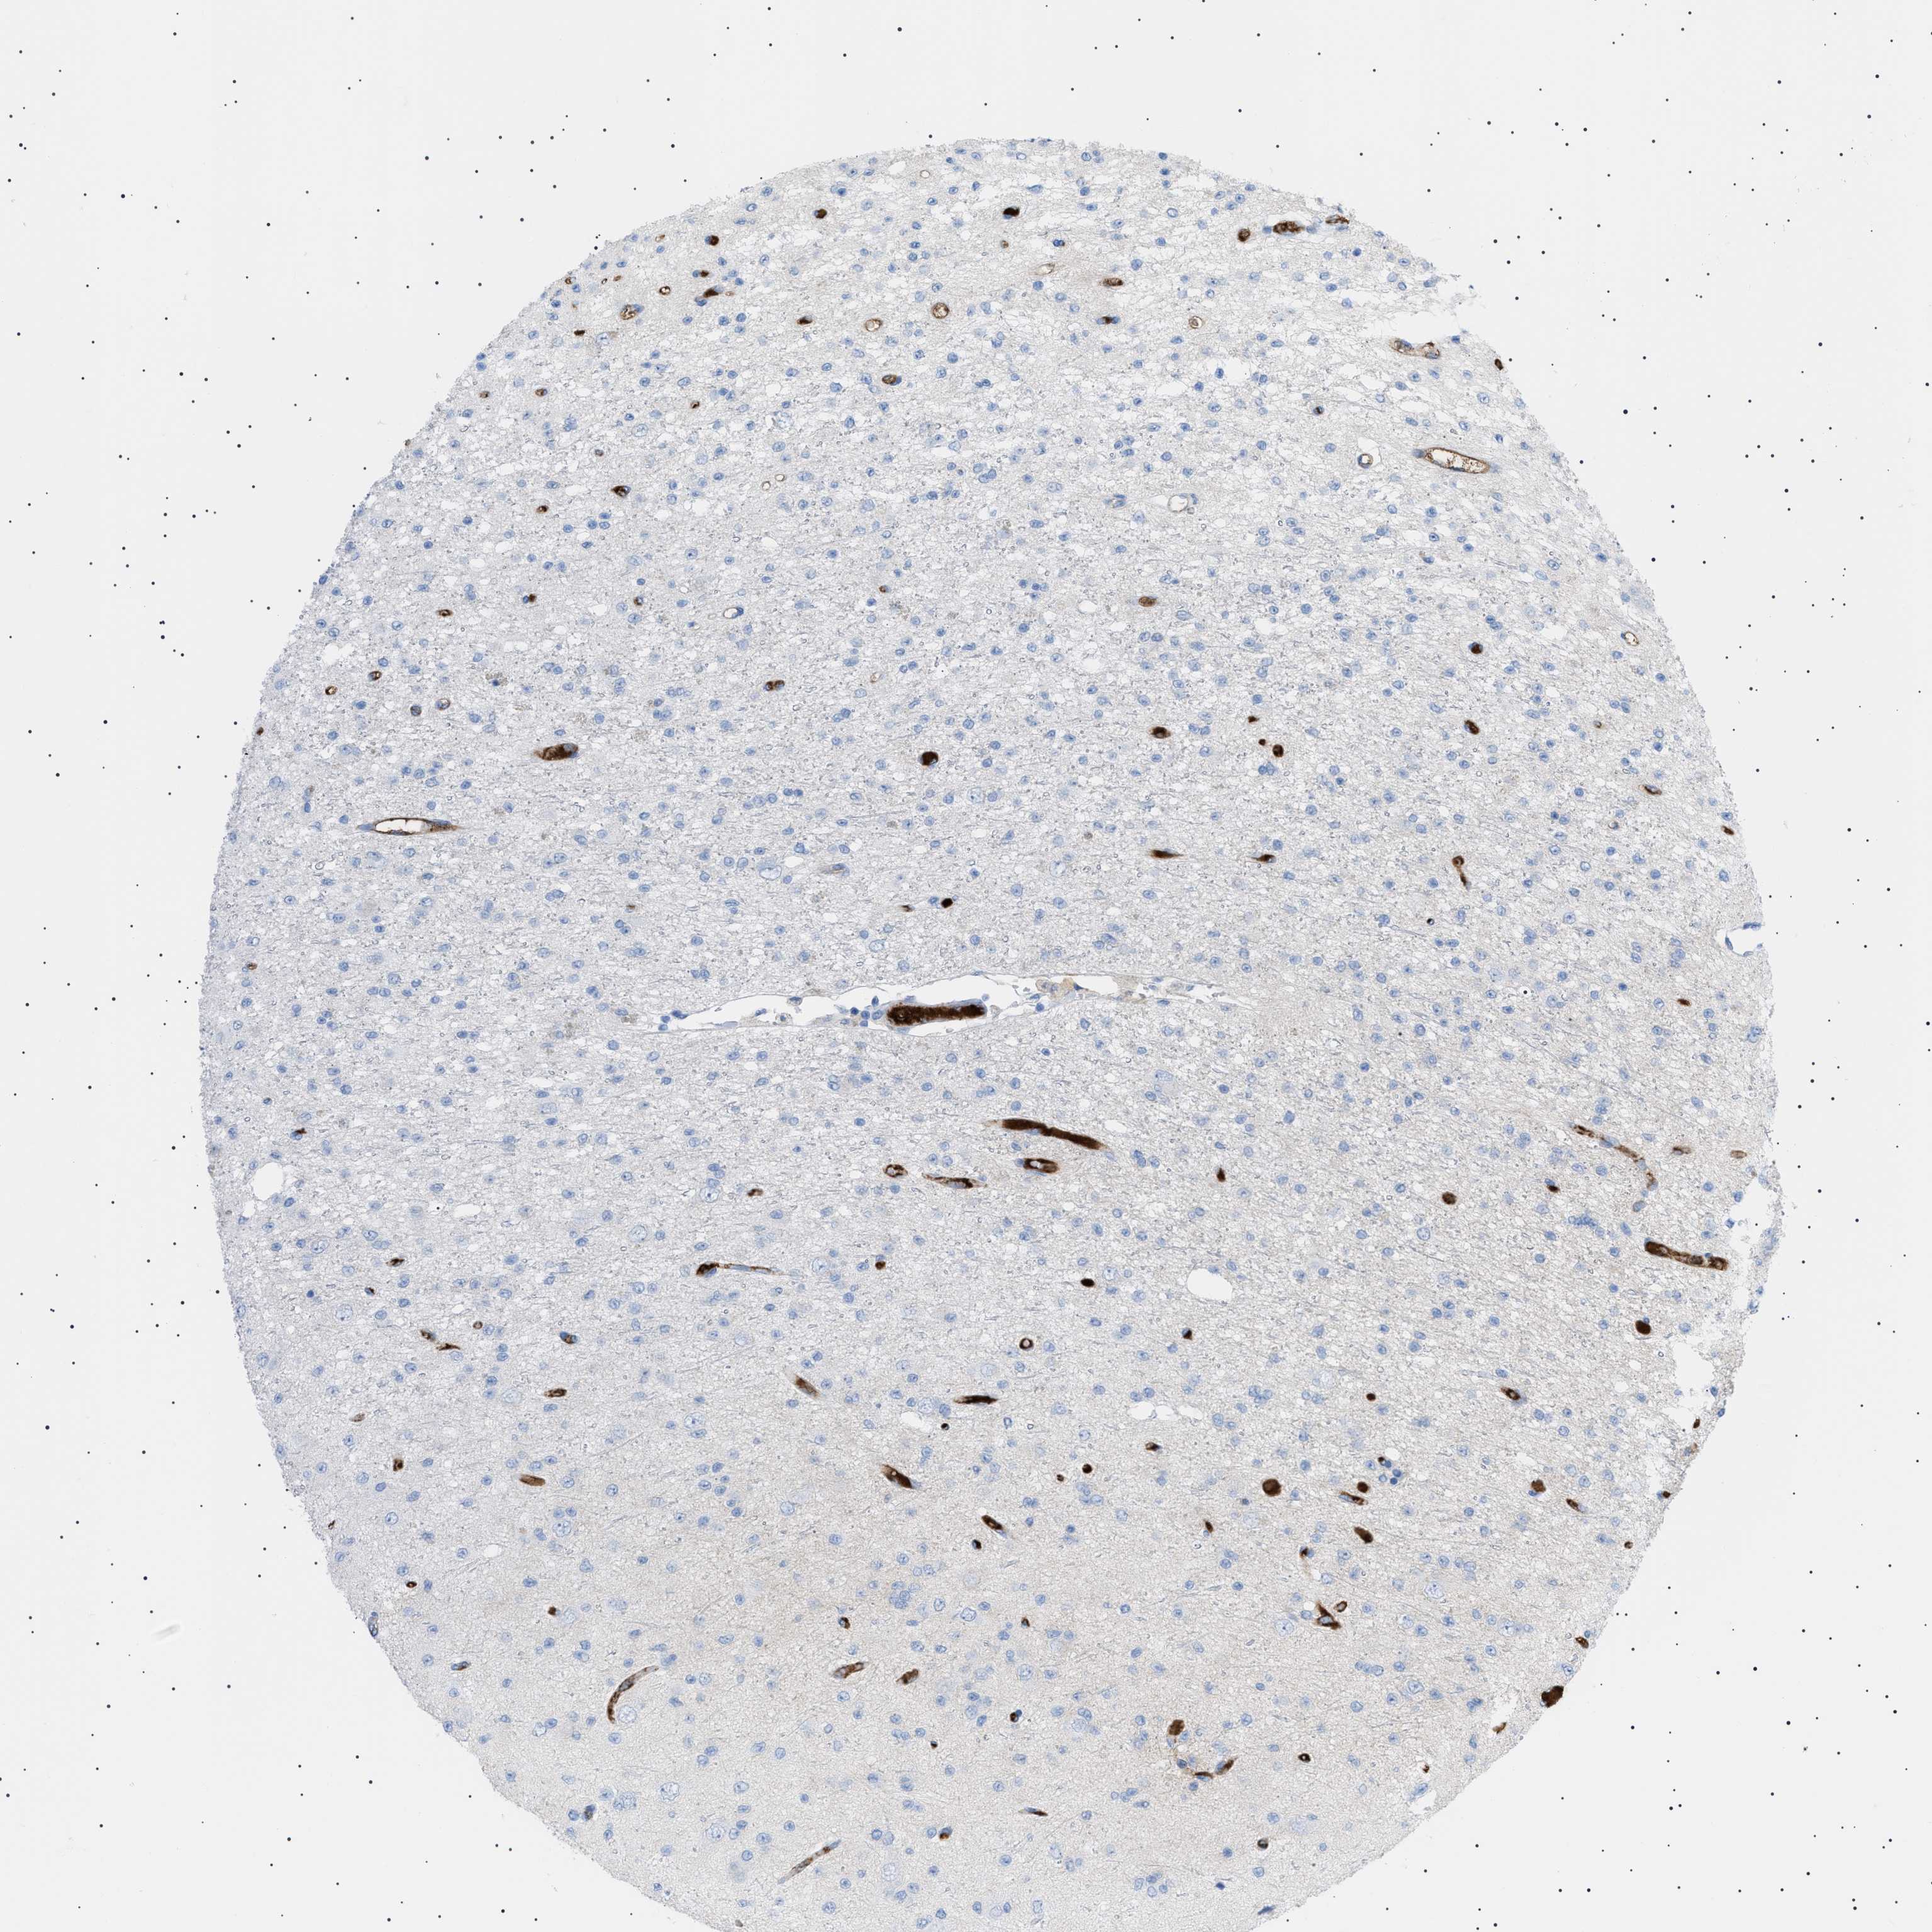

GLIOMA - Protein expressioni

A mouse-over function shows sample information and annotation data. Click on an image to view it in a full screen mode. Samples can be filtered based on level of antibody staining by selecting one or several of the following categories: high, medium, low and not detected. The assay and annotation is described here.

Note that samples used for immunohistochemistry by the Human Protein Atlas do not correspond to samples in the TCGA dataset.

Antibody stainingi

Antibody staining in the annotated cell types in the current human tissue is reported as not detected, low, medium, or high, based on conventional immunohistochemistry profiling in selected tissues. This score is based on the combination of the staining intensity and fraction of stained cells.

Each image is clickable and will lead to virtual microscopy that enables deeper exploration of all samples and also displays staining intensity scores, fraction scores and subcellular localization as well as patient and tissue information for each sample.

Antibody HPA060604

Antibody CAB016072

Glioma, malignant, Low grade

Glioma, malignant, High grade